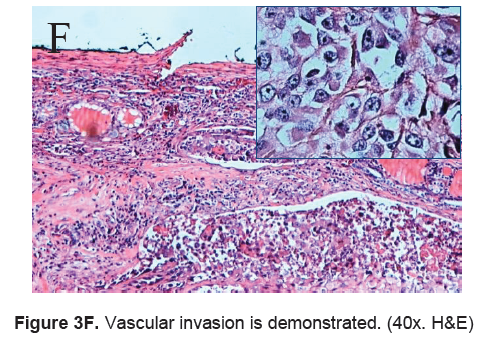

The right lobe measured 8.3 x 6.0 x 4.3 cm, and weighed 119.5 grams with a tan brown surface covered with fibrous tags (Figure 3A). Cut sections showed an ovoid mass, 6.7 x 5.2 cm in greatest dimensions, with a thin capsule and yellow-tan, gritty to mucoid cut surface with areas of hemorrhage and necrosis. The tumor infiltrated and replaced normal thyroid parenchyma and was surrounded by a thin capsular rim. Tissue sections of the right lobe revealed an infiltrative tumor composed of an admixture of pleomorphic cells, spindle cells and occasional tumor giant cells (Figure 3B). There were small areas showing reminiscent papillary or microfollicle pattern, while some areas showed large epithelioid or multinucleated tumor cells with bizarre nuclei (Figure 3C). Capsular (Figure 3D) and vascular (Figure 3F) invasion were present with extensive tumor necrosis. The uninvolved right and left lobes showed multinodular colloid goiter with lymphocytic thyroiditis. It was signed out as an Anaplastic (undifferentiated) thyroid carcinoma of the right lobe.

Click here to download Figure 3F

Figure 3F. Vascular invasion is demonstrated. (40x. H&E)